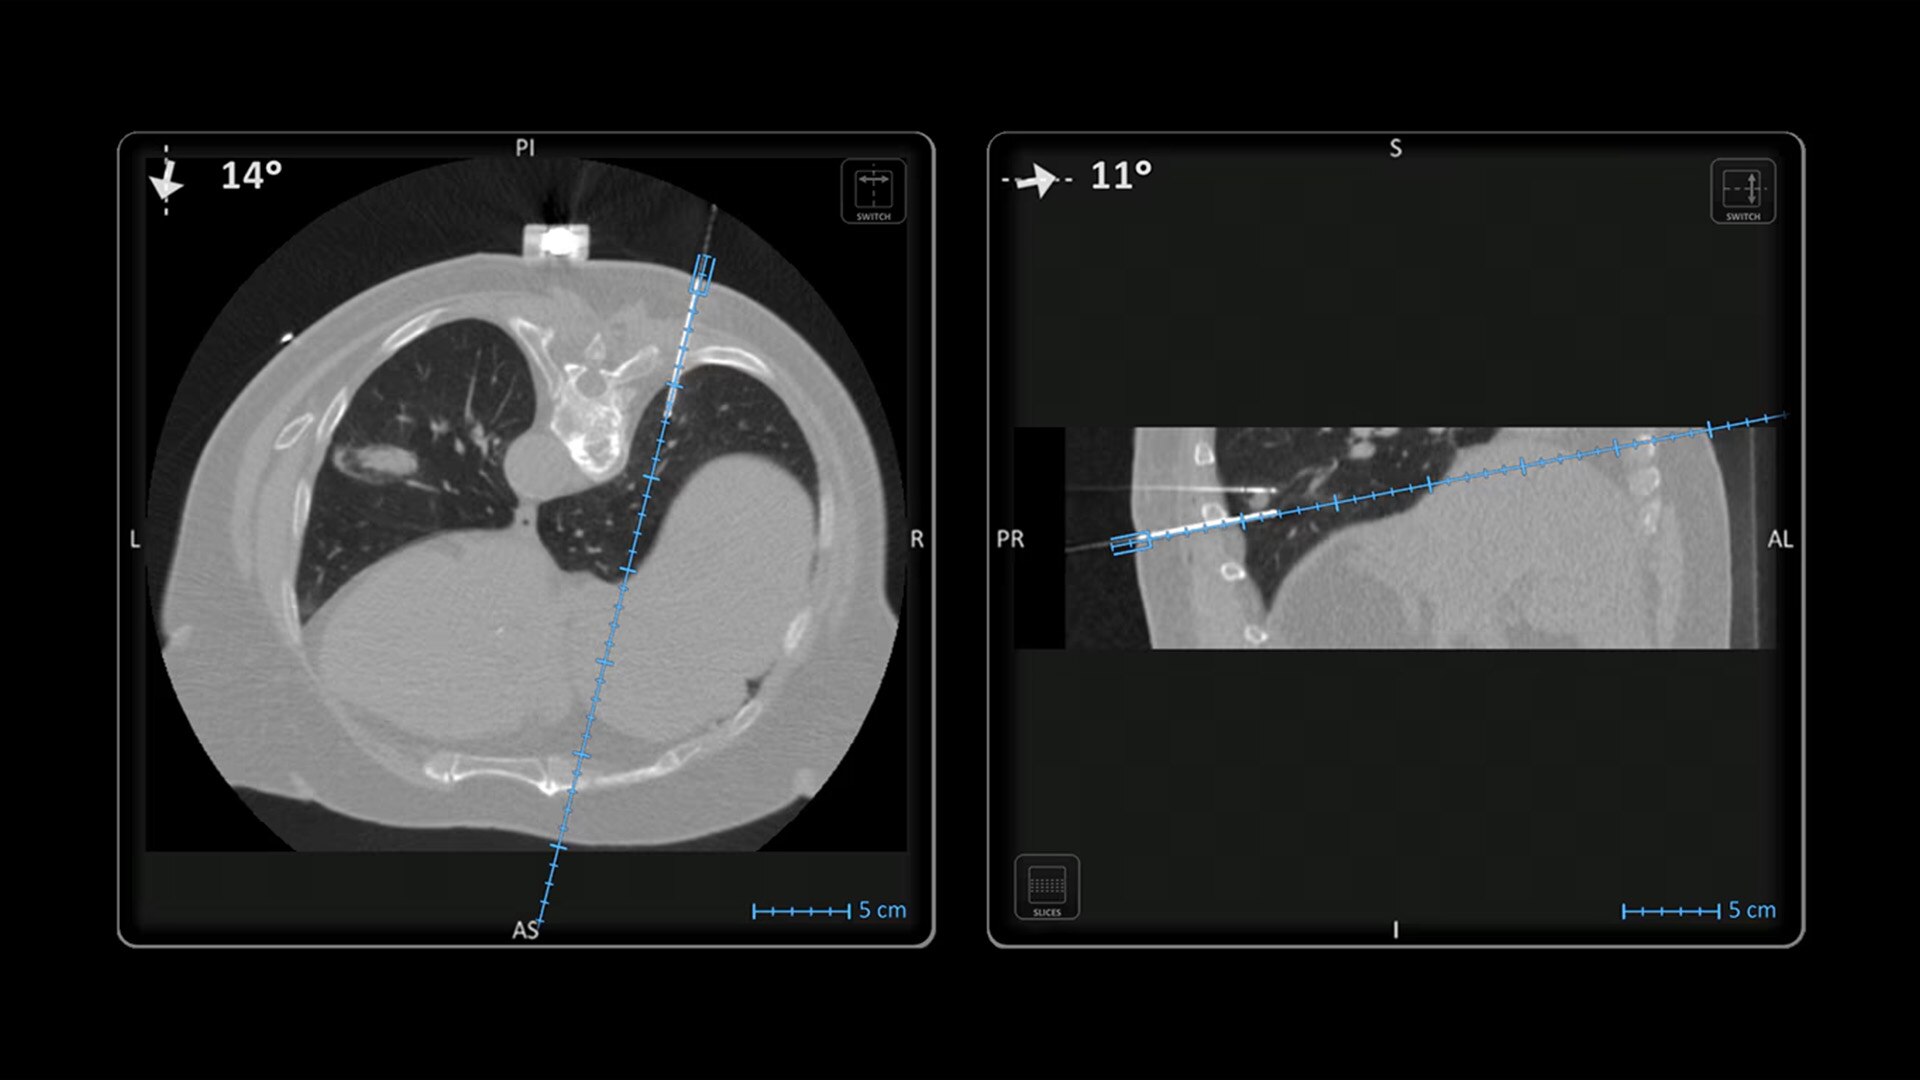

Imactis enables you to find the ideal path to the target.

With real-time image reconstruction, live interactive navigation and no limit in angulation, the optimal clinical choices are clear.

Live 3D needle tracking, precise reproduction of your planned trajectory and continuous needle depth measurement help ensure optimal needle placement.